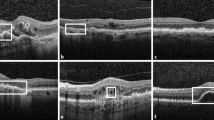

Macular hyperautofluorescent rings identified by AF imaging, using a 488 nm laser excitation light, were measured manually by outlining horizontal borders with the Heidelberg Eye Explorer Software (HEYEX, Heidelberg Engineering). Furthermore, the software was used to measure the extent of the foveal EZ (based on central foveal scan) on OCT imaging. Exemplary AF and corresponding OCT images are provided in Supplementary Fig. 1.

On OCT scans recorded along the horizontal meridian, the width of the visible ellipsoid zone was negatively correlated with age (slope = − 45.37 ± 8.14 µm/year; R2 = 0.65) (Fig. 1b). By visual inspection, this effect seemed more pronounced in patients below the age of 20 years than in older patients. The width of the ellipsoid zone was positively (p < 0.001) correlated with visual acuity (slope= 2729.1 ± 593.5 µm per decimal unit BCVA; R2 = 0.56; p < 0.001) (Fig. 1c).

A symmetrical macular hyperautofluorescent ring using AF imaging was identified in 13 out of the 17 (76%) patients, the other 4 patients revealed either diffuse (n = 2) or patchy chorioretinal (n = 2) alterations on AF imaging. Patients with a hyperautofluorescent ring were younger (median age 21 vs. 54 years; p = 0.003) and had a better visual acuity (median BCVA 0.4 vs. 0.063; p = 0.0004) than patients without a ring. The horizontal measured diameter of the ring was negatively correlated with age (117.32 µm/year; R2 = 0.72; p < 0.001) which seemed by visual inspection more pronounced in patients below the age of 20 years (Fig. 1d) and positively correlated (p = 0.03) with visual acuity (slope = 4909 ± 1062 µm per decimal unit BCVA; R2 = 0.63; p < 0.001) (Fig. 1e).